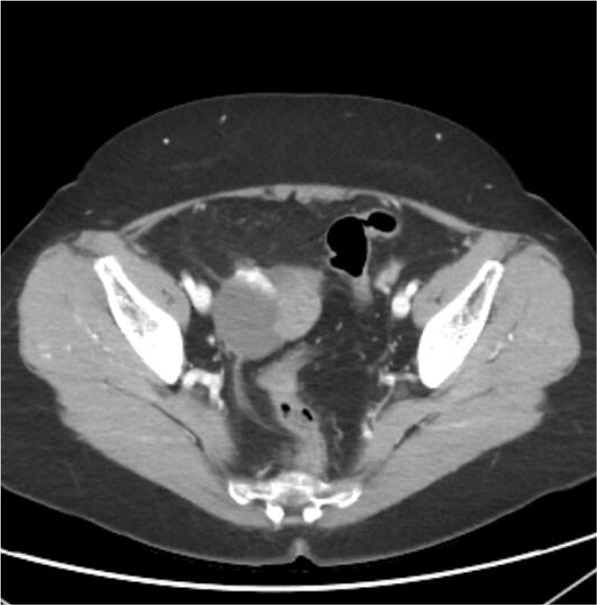

• TC toraco-abodmino-pélvico: masa ovárica derecha con metástasis linfáticas, retroperitoneales e iliacas derechas, probable estadio IIIa1 de la FIGO.

Carcinoma de ovario derecho seroso de alto grado, estadio IIIa de la FIGO.